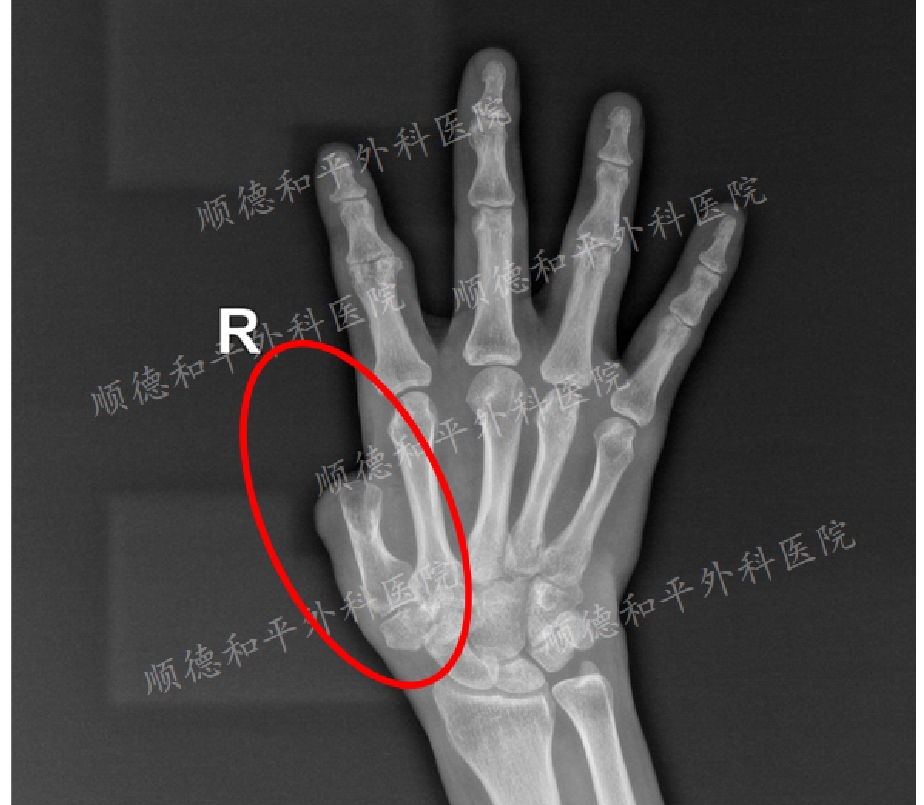

再造手指主要目的是为了恢复手的功能、感觉,兼顾外观。没有感觉的手指不仅常易致伤(烫伤、刺伤),而且功能也严重受限,尤其是指尖的捏物与抓握,同时,有力的伸屈是手指运动功能的重要方面。

以往过分强调功能而忽视外形,顺德和平外科医院的手指再造术,除了恢复手指功能,还兼顾手指美观。无论男女老少,有一个外形美观

的再造手指,才会无忧无虑地更大限度地去应用。 顺德和平外科医院手外科中心简介